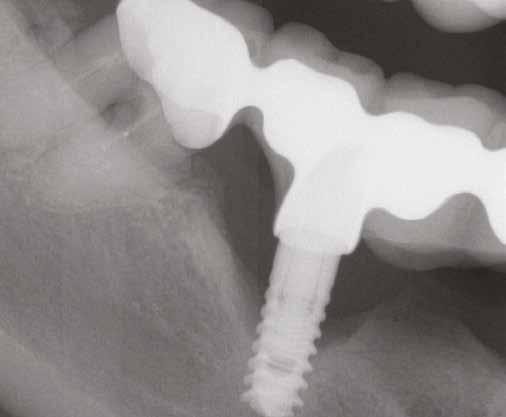

tottuk (az okklúziós koncepciók alapján az implantációs pótlások nem voltak vezető fogak, és csak könnyű érintkezéseket alakítottunk ki, amelyeket artikulációs papírral ellenőriztünk). A páciensek instrukciókat kaptak a megfelelő szájhigiénére vonatkozóan, összpontosítva a fogköz kefékkel történő tisztítására. Végső kontroll röntgenfelvétel készült. A PEEK felépítmény nem radioopák, így az implantátum és a korona közötti távolság könnyen meghatározható a röntgenfelvételen: a felépítmény megfelelően illeszkedik az implantátumban, ha az implantátum válla és a korona alsó széle közötti rés 0,55 mm a röntgenfelvételen (8–11. ábra)

8. a–b. ábra: Végső röntgenfelvétel az implantátum helyzetéről (a) és a szájon belüli végső szituáció az 1. esetről (b).

9. a–b. ábra: Végső röntgenfelvétel az implantátum helyzetéről (a) és a szájon belüli végső szituáció a 2. esetről (b).

10. a–c. ábra: Végső röntgenfelvétel az implantátum helyzetéről (a) és a szájon belüli végső szituáció a 3. esetről (b és c).

11. a–b. ábra: Végső röntgenfelvétel az implantátum helyzetéről (a) és a szájon belüli végső szituáció a 4. esetről (b).